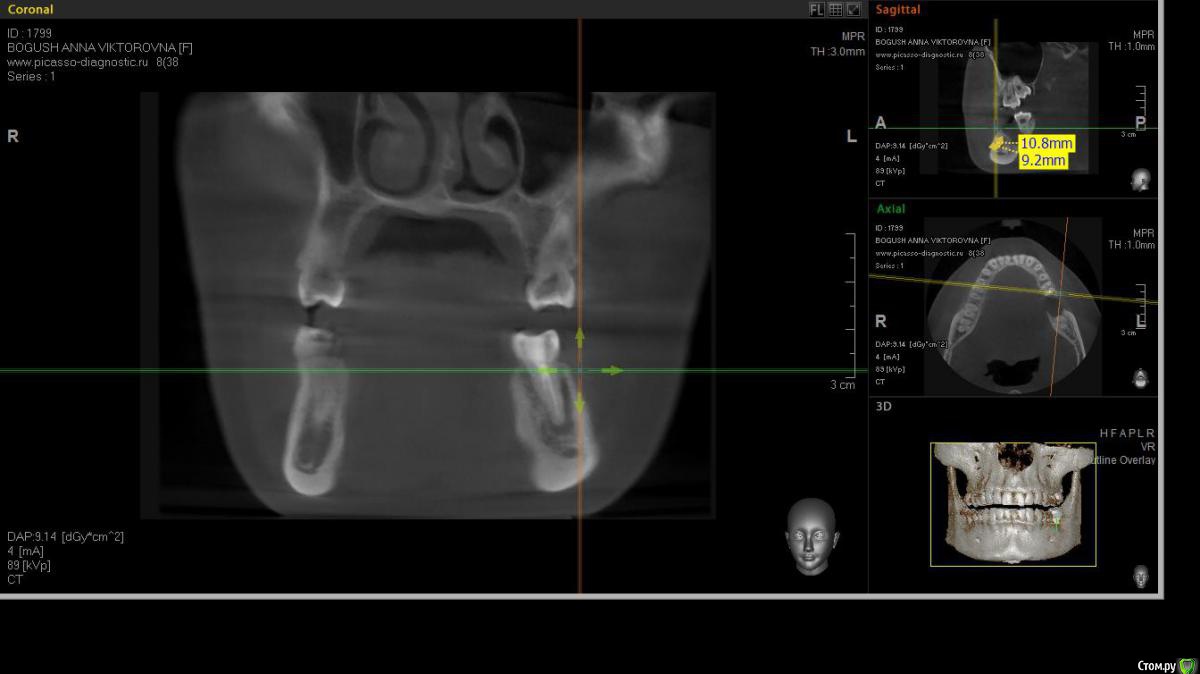

cor Опубликовано 2 апреля, 2016 Поделиться Опубликовано 2 апреля, 2016 Доброго времени суток, коллеги! Каков Ваш прогноз? Удалять пац. совсем не хочет(знакомая). Есть хоть какая то вероятность, что ретрит поможет? <script> </script> Ссылка на комментарий

cor Опубликовано 2 апреля, 2016 Поделиться Опубликовано 2 апреля, 2016 (изменено) гадская вирусятина на компе мешает. Нет конечно желающих. Но если ретрит будет, то делать его буду я. Но слабо верю в положительный исход(( Изменено 2 апреля, 2016 пользователем cor Ссылка на комментарий

Гарриевич Опубликовано 3 апреля, 2016 Поделиться Опубликовано 3 апреля, 2016 Доброго времени суток, коллеги! Каков Ваш прогноз? Удалять пац. совсем не хочет(знакомая). Есть хоть какая то вероятность, что ретрит поможет? шансов не меньше чем тут Ссылка на комментарий

St. Опубликовано 3 апреля, 2016 Поделиться Опубликовано 3 апреля, 2016 Доброго времени суток, коллеги! Каков Ваш прогноз? Удалять пац. совсем не хочет(знакомая). Есть хоть какая то вероятность, что ретрит поможет? Вполне есть смысл попробовать. Вероятность есть, только "заживать" будет долго. Ссылка на комментарий

cor Опубликовано 5 апреля, 2016 Поделиться Опубликовано 5 апреля, 2016 Почему?Наверное потому что такие объемные очаги ещё не перилечивал. Но деваться некуда, будем пробовать. Ссылка на комментарий

Л Ю С Я Опубликовано 5 апреля, 2016 Поделиться Опубликовано 5 апреля, 2016 Наверное потому что такие объемные очаги ещё не перилечивал. Но деваться некуда, будем пробовать.Уже не раз писали, что размер не имеет значения)))). Не надо перелечивать очаг. Ваша задача пройти, правильно сформировать, очистить и запаковать каналы, а также правильно восстановить коронковую часть. И будет вам хилинг))) 2 Ссылка на комментарий